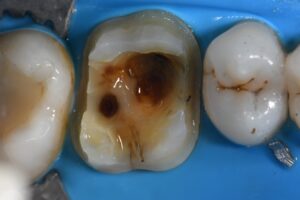

August 29, 2022 Full coverage to eliminate peripheral rim fractures emanating from this old amalgam. GC’s LiSi used in this situation with HDM (High Density Micronization) technology for equal dispersion of silicate crystals. #GCLiSi #TheShinEffect Previous Post Next Post